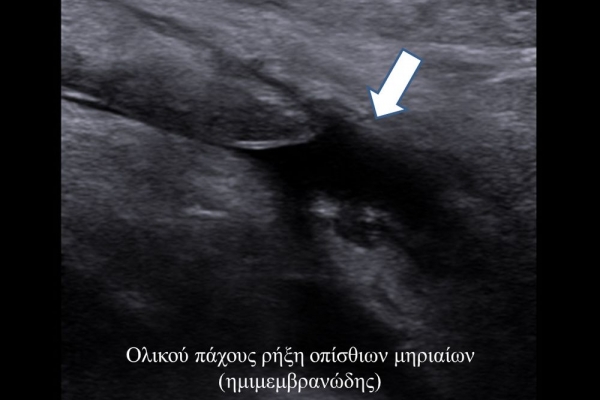

Είναι μια νέα μέθοδος που χρησιμοποιεί υψηλής ευκρίνειας υπερήχους για τη διάγνωση μυοσκελετικών παθήσεων που αφορούν τένοντες, μυς, συνδέσμους, νεύρα και περιφερικές αρθρώσεις. Η μέθοδος αναπτύχθηκε τα τελευταία χρόνια και αποτελεί αναπόσπαστο μέρος στη διαφορική διάγνωση παθήσεων που αφορούν τηνορθοπαιδική, αθλητιατρική, ρευματολογία και παιδιατρική.

Πρόκειται για υπερηχογράφημα υψηλής ευκρίνειας που επιτρέπει την λεπτομερέστατη απεικόνιση (σε επίπεδο χιλιοστού) ακόμη και πολύ μικρών/επιφανειακών ανατομικών δομών και απαιτεί ειδικό υπερηχογραφικό εξοπλισμό καθώς και εξειδίκευση του ακτινολόγου. Η εξέταση γίνεται με δυναμικό τρόπο, δηλ εκτελούνται δοκιμασίες κίνησης του μέλους που πάσχει, ώστε να αποκαλυφθεί η παθολογίαακόμη και όταν δεν είναι εμφανής σε θέση ηρεμίας. Επιπλέον, η εξέταση είναι ανώδυνη και ασφαλής και δεν περιλαμβάνει ακτινοβολία (CT), μαγνητικό πεδίο (MRI) ή παραμονή σε κλειστό χώρο και είναι πολύ ανεκτή τόσο σε ενήλικες όσο και σε παιδιά.

- Παθήσεις Ώμου (πχ ρήξη στροφικού πετάλου)